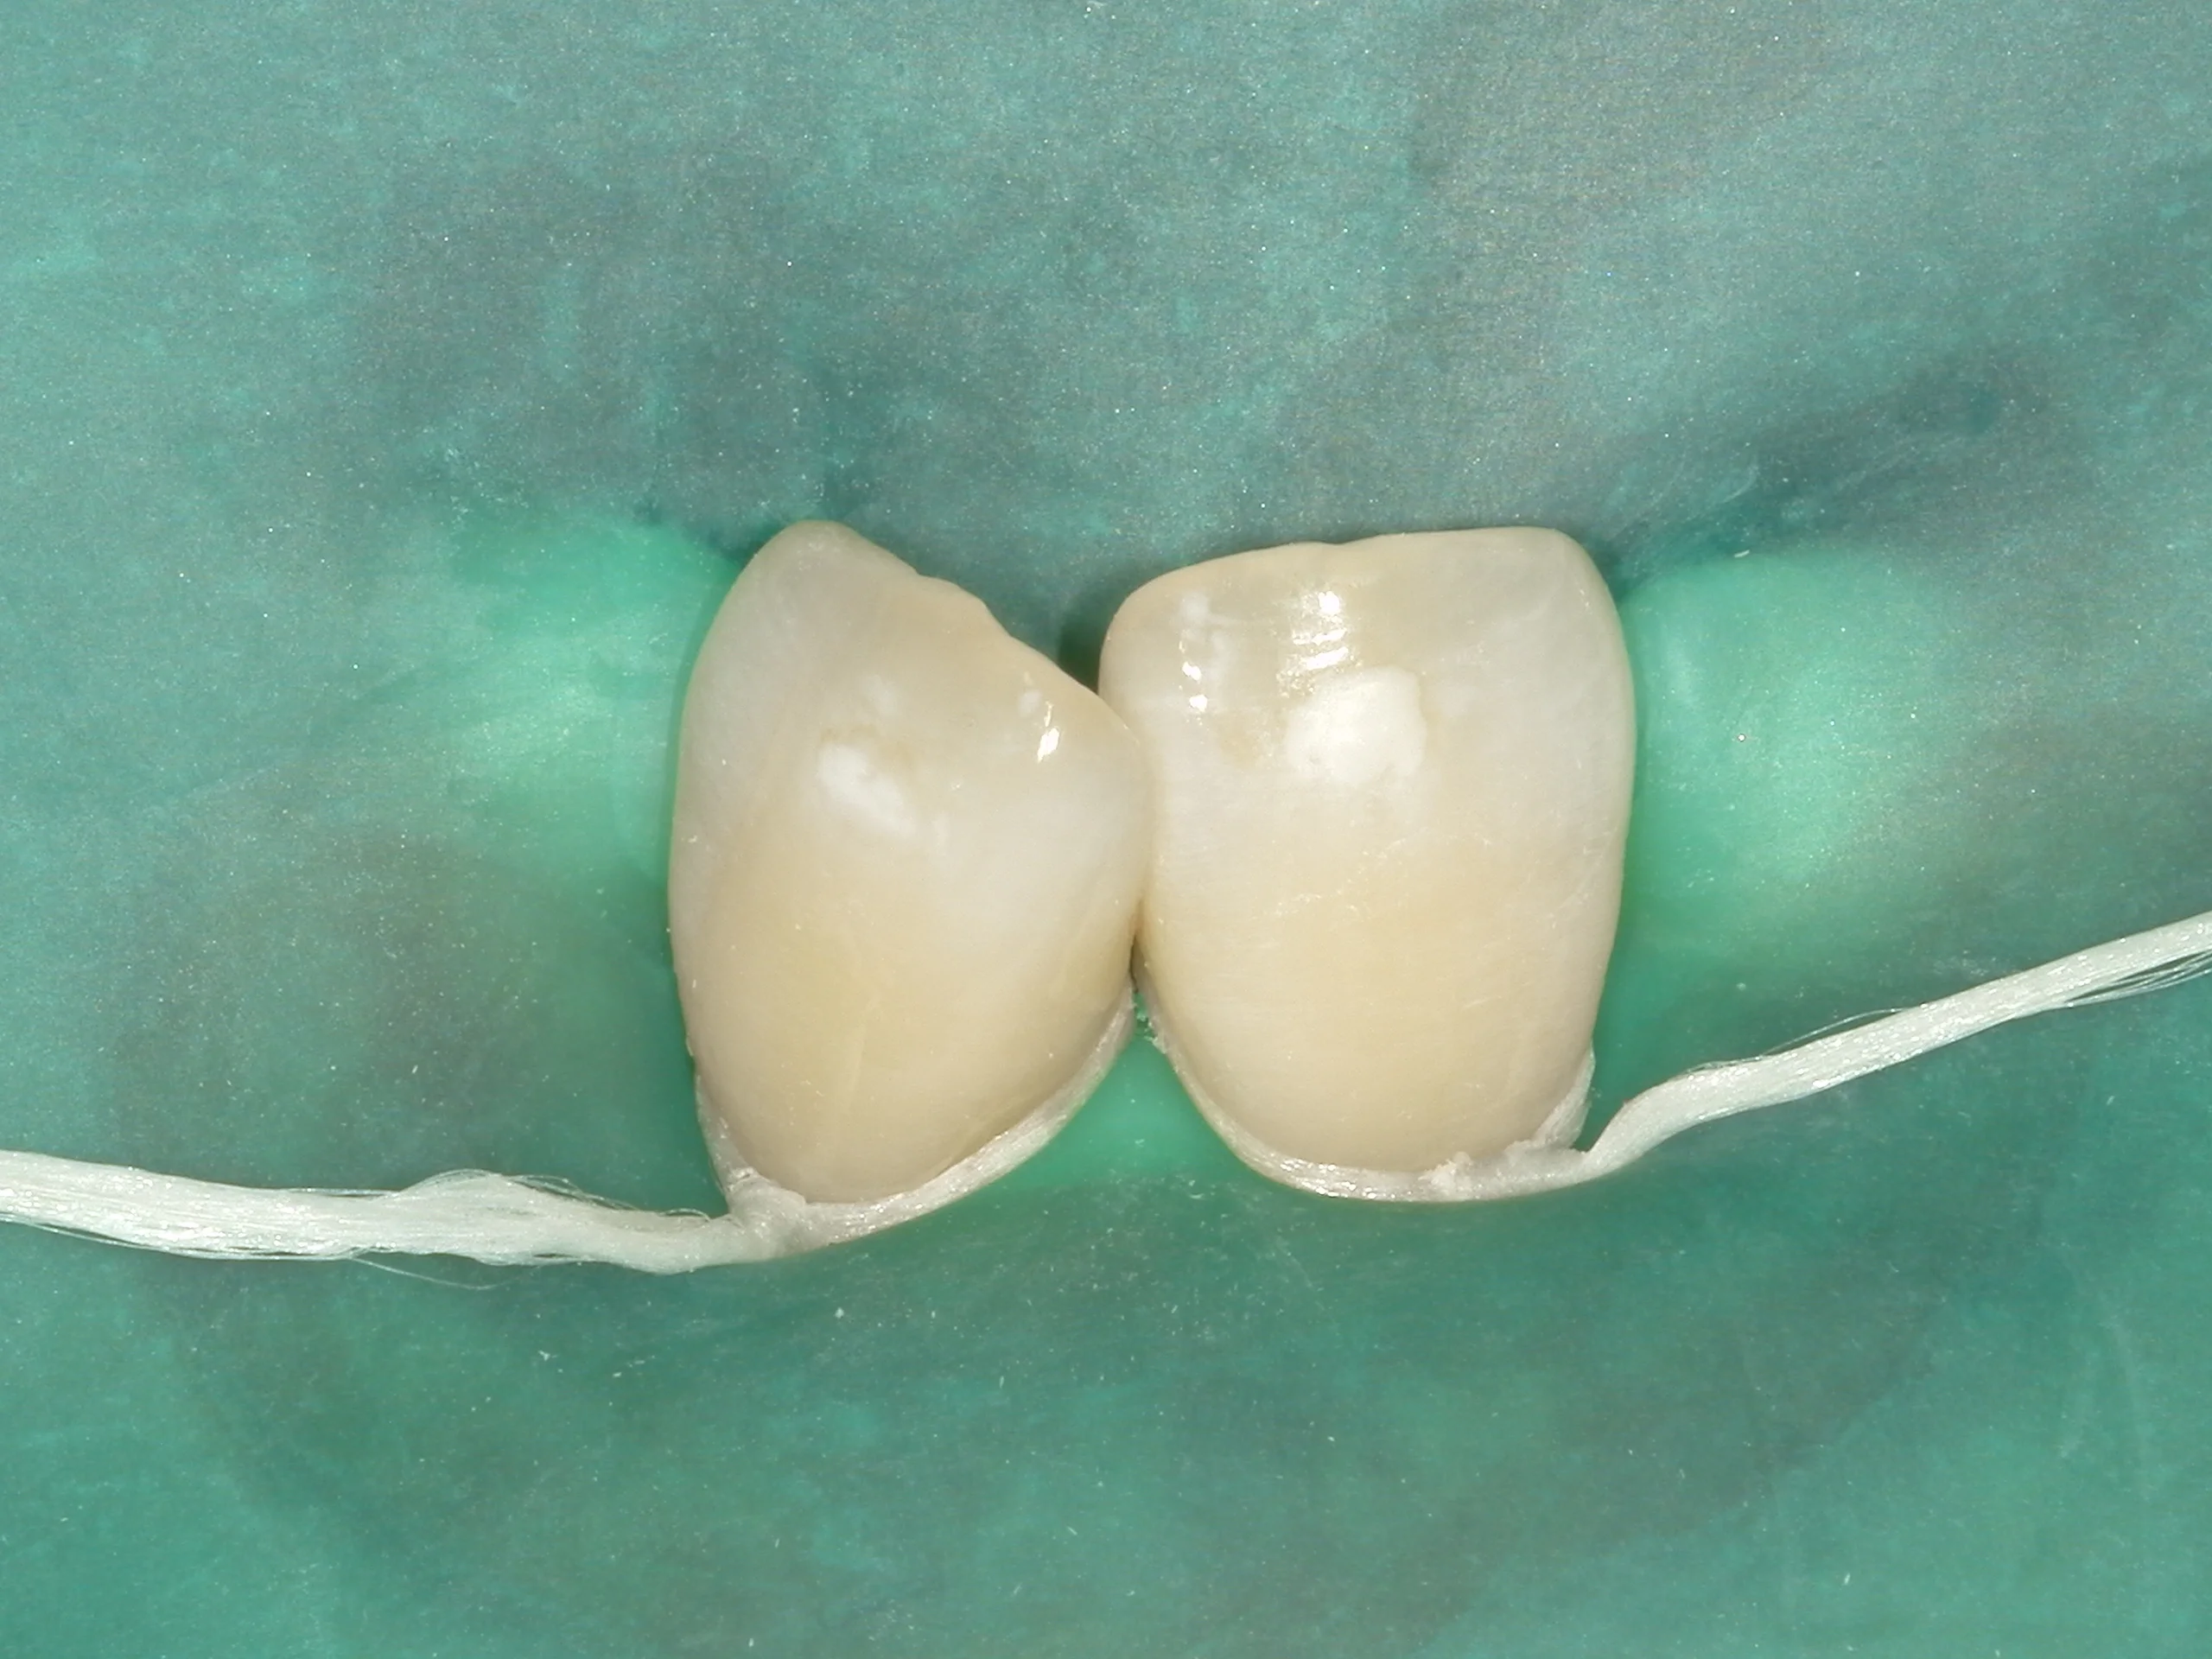

まずはこんな感じで・・・

ラバーダムというゴムのマスクを装着します。

というのも、ICONで使用する薬剤の中に塩酸15%溶液があります。

多くの方はなんとなくイメージできるかと思いますが、塩酸は強い酸性で歯茎や唇に当たるとやけどをしてしまいます。

そうならないためにこのようにしっかりと封鎖する必要があるのです。